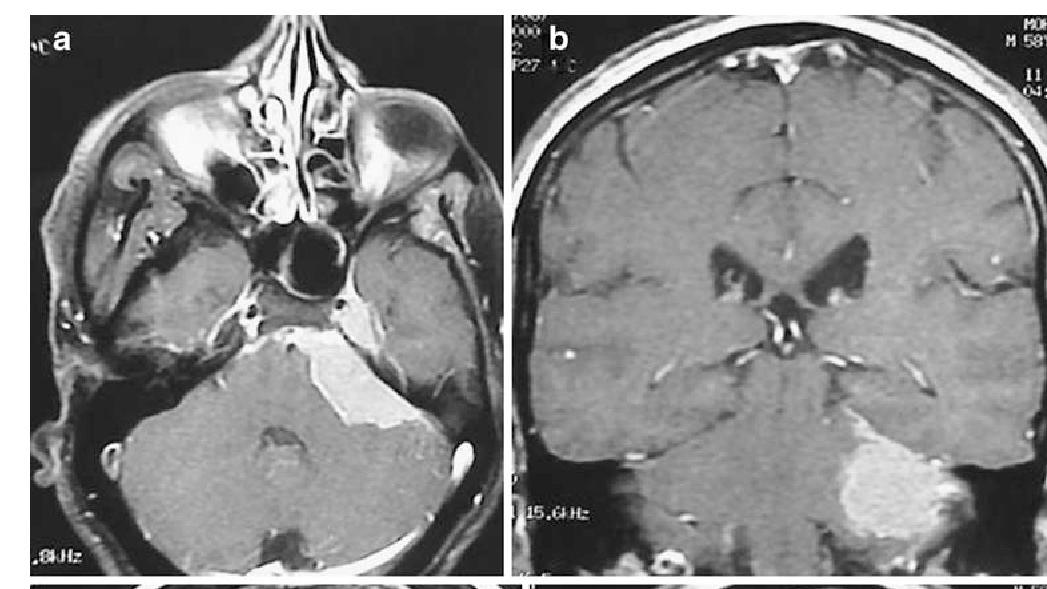

俗稱為後尾枕的枕骨,位於頂骨之後並延伸至顱骨底部,下方有一個名為枕骨大孔的大洞,是腦幹與脊髓的交匯之處。而枕骨大孔腦膜瘤就是指生長在枕骨大孔四周的腦膜瘤,大部分出現在枕骨的前緣,可以向上發展走入頭顱,亦可向下生長進入頸椎管之內。

枕骨大孔腦膜瘤的治療以手術切除為主。假如腫瘤生長在背側位置,可採用後正中入路;若腫瘤在延髓前面或側方,則需要遠外側入路。無論採用哪一種方法,都要明白枕骨大孔的空間有限,卻有很多重要的組織和神經與腫瘤迫在一起,包括腦幹、延髓、包括第九至十二條腦神經的下路神經線,以及椎頸動脈和其分叉血管走過。故此執刀的神經外科醫生一定要全面了解枕骨大孔的解剖學,亦要有熟練的技術操作顯微鏡手術,才能有效切除腫瘤的同時,而又能保留附近組織及神經線的功能。

手術期間,為了顯露出腫瘤,以取得安全的手術空間,醫生需要將部分枕骨及寰椎橫突切除,而採取遠外側入路更需要將一邊的椎動脈推開,甚至要將枕髁磨除,從而擴闊空間,讓醫生可以清楚看到腫瘤及其他組織,減低手術的深度。假如枕髁磨走的範圍超過一半,手術後需要進行枕頸的融合術,以維持頭頸的穩定性。